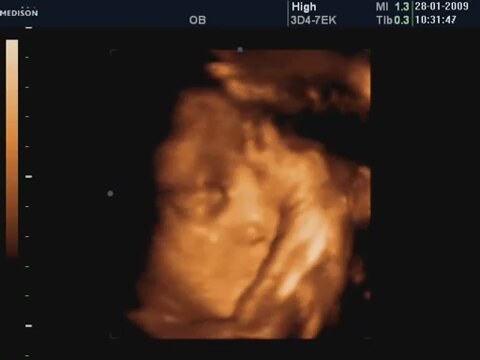

32 Haftalık Bebeğin 4 Boyutlu Ultrason Görüntüsü